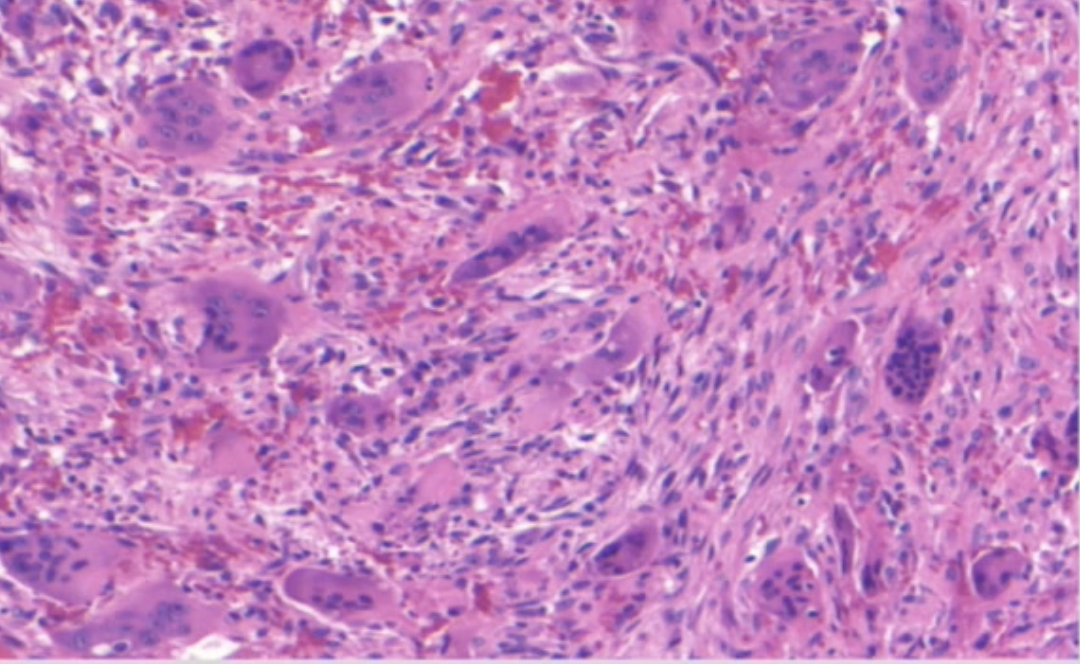

what are the areas with numerous purple circles

multinucleated giant cells

multinucleated giant cells histology is associated with

CGCG

cherubism associated with

histology looks the same

CGCG, brown tumor of hyperparathyroidism, cherubism